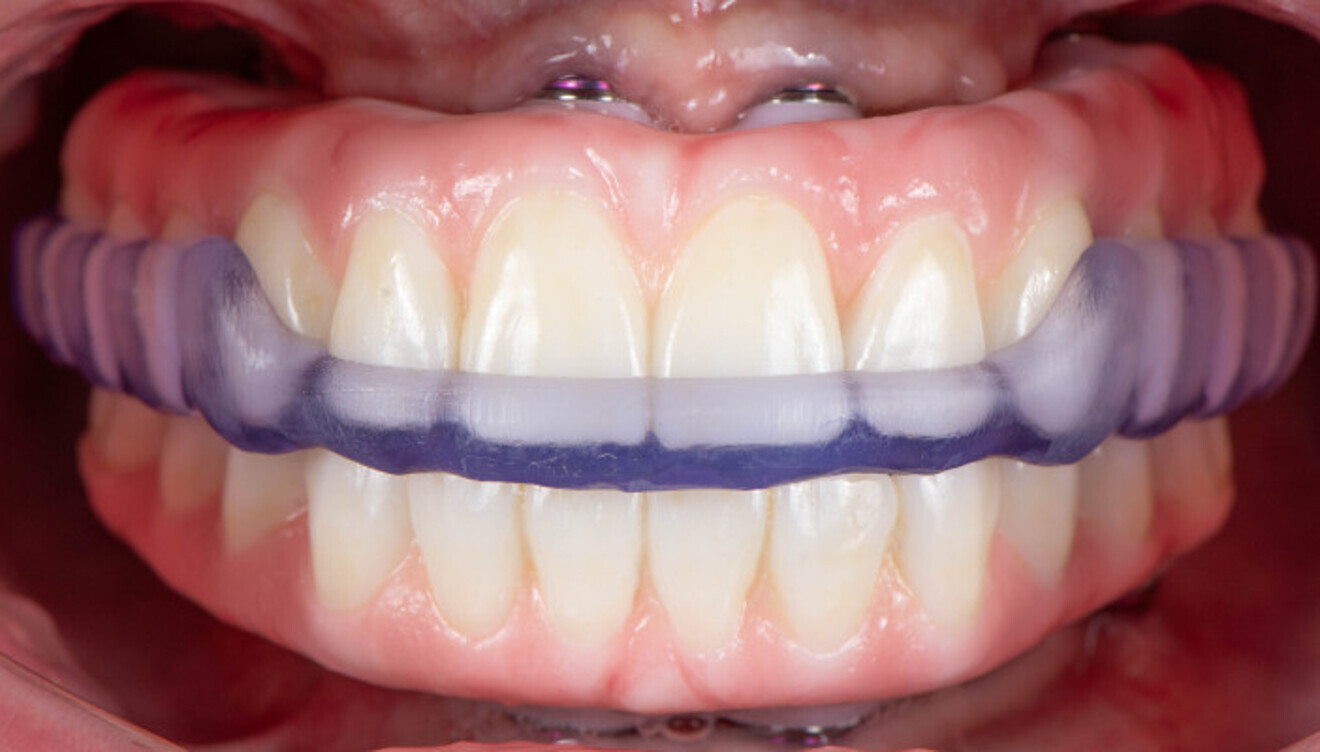

Before surgery, an intra-oral scanner was employed to acquire the digital data for the design of the temporary prostheses (Fig. 7). The teeth were digitally removed, and digital prostheses were created. The data of the virtually constructed prostheses was subsequently transmitted to a milling machine for the fabrication of monolithic PMMA prostheses.

The treatment was carried out under local anaesthesia with 2% lidocaine and 1:100,000 adrenaline. A crestal incision was made and a full-thickness mucoperiosteal flap raised. The implant beds were prepared with the Straumann Surgical Cassette, and two Straumann BLX implants (4.5 × 10.0 mm, SLActive, Roxolid) and two Straumann zygomatic implants (4.3 × 40.0 mm) were placed in the maxilla (Fig. 8). Following the same protocol, four Straumann BLX implants (4.5 × 10.0 mm, SLActive, Roxolid) were inserted in the mandible. Straumann screw-retained abutments were positioned on to the implants (Fig. 9).